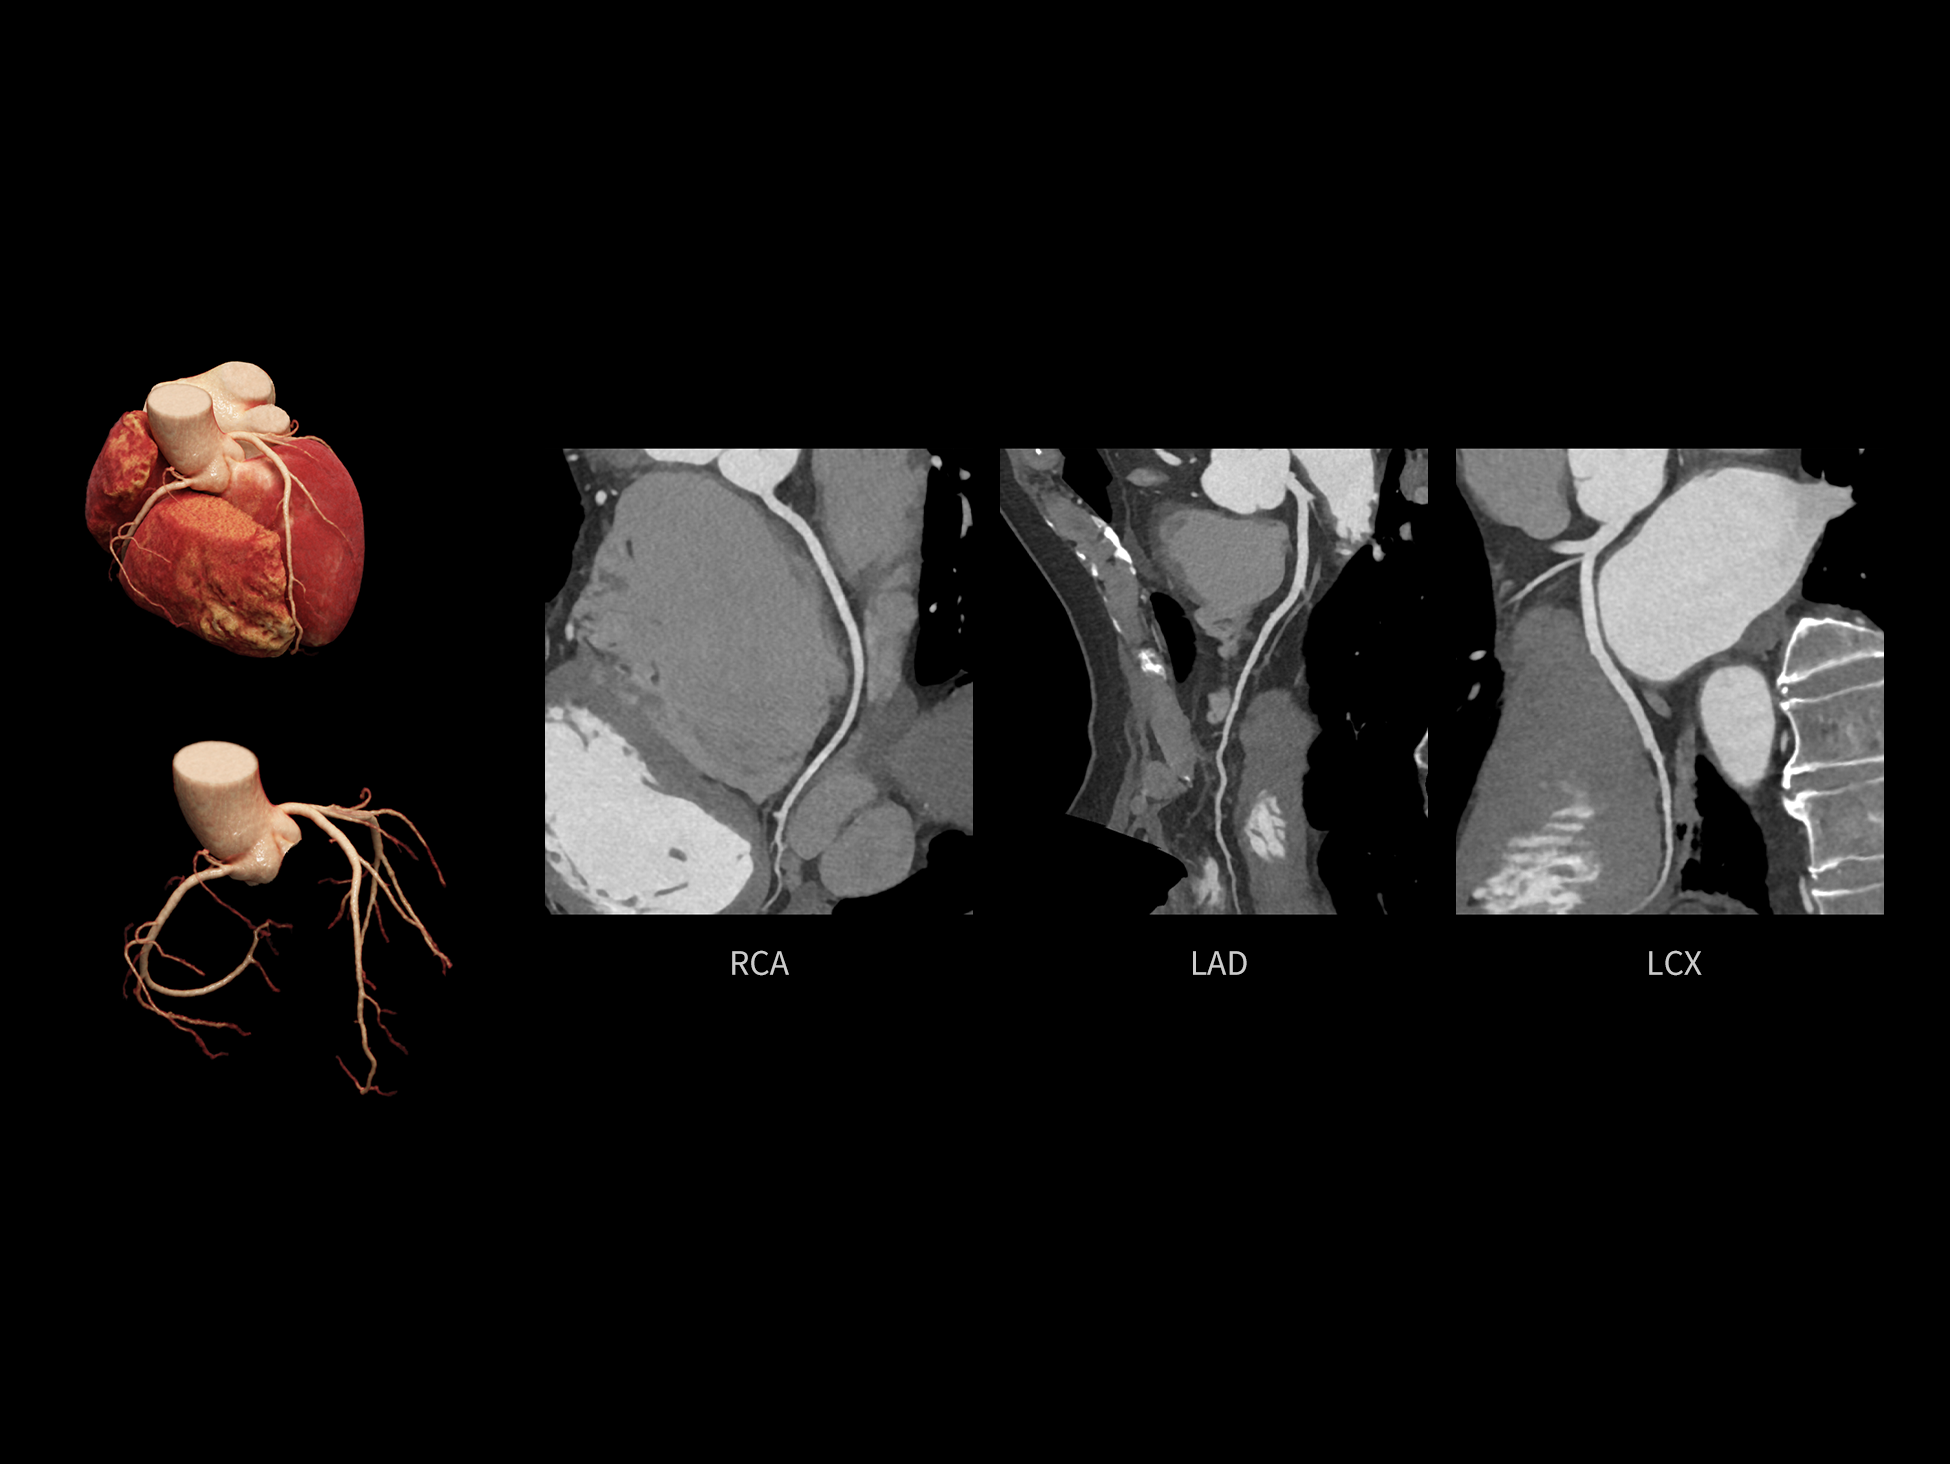

CardioCapture 2.0 通过“识别–追踪–建模–校正”的完整流程,精准分割心脏结构,动态追踪运动轨迹,并构建多时相运动场,最终实现冠脉、瓣膜、心肌及心室结构的同步校正,清晰洞见每一次心跳细微变化,真正将心脏动态掌握于毫秒之间。

CardioCapture 2.0 在目标时相前后重建多时相影像,通过深度学习网络精准提取冠脉中心线,进而建立时相间运动模型,实现对冠脉分段图像的精准运动校正。

CardioCapture 2.0 可对心肌、瓣膜及心室等结构进行同步运动校正。基于深度学习的心脏精细分割,实现了更完整的心脏全局信息提取,能有效抑制全心运动伪影,显著提升心脏细节的清晰度与诊断可靠性。

冠脉运动校正

全心结构运动校正

心脏成像,自由掌控

uCT SiriuX® 以 8ms 全心等效时间分辨率与16cm宽体覆盖,突破传统心脏成像局限,完整呈现搏动中的心脏结构与动态功能;配合无心电门控扫描与智能化工作流,更使心脏检查摆脱心率、配合度与操作复杂度的束缚,实现真正自由从容的成像体验,为临床功能评估提供更深层依据。